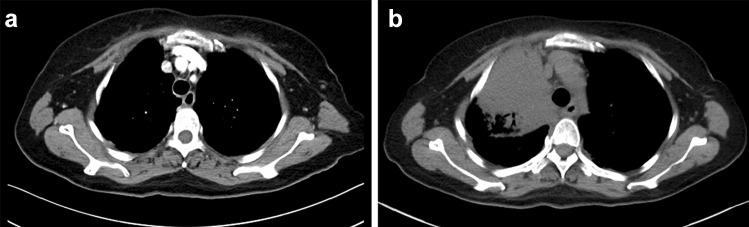

Ceritinib is a new anaplastic lymphoma kinase (ALK) inhibitor that has shown greater potency in patients with advanced ALK-rearranged non-small cell lung cancer, including those who had disease progression in crizotinib treatment. Here we reported, after several months of ceritinib treatment, two patients with advanced ALK-rearranged pulmonary adenocarcinoma exhibited a spectrum of respiratory symptoms like cough and dyspnea, with significantly higher inflammatory indicators. Chest computed tomography (CT) showed multiple bilateral and peripheral lesions in lungs. The prior considerations taken into account were disease progression or infection. However, biopsies of the pulmonary nodules revealed features of granulomatous inflammation without definite cancer cells. We documented for the first time that ceritinib might be associated with pulmonary granulomatous inflammation, and clinicians should be alert to the possibility that the rare adverse event emerged during ceritinib treatment.

塞瑞替尼是一种新型的间变性淋巴瘤激酶(ALK)抑制剂,在晚期ALK 重排的非小细胞肺癌患者中显示出更强的疗效,包括那些在克唑替尼治疗中疾病进展的患者。在这里,我们报告了两名晚期ALK 重排肺腺癌患者在接受塞瑞替尼治疗几个月后出现了一系列呼吸系统症状,如咳嗽和呼吸困难,同时炎症指标显著升高。胸部计算机断层扫描(CT)显示肺部多个双侧和外周病变。先前考虑的因素包括疾病进展或感染。然而,肺部结节的活检显示出肉芽肿性炎症的特征,没有明确的癌细胞。我们首次记录到塞瑞替尼可能与肺肉芽肿性炎症有关,临床医生应该警惕在塞瑞替尼治疗期间出现这种罕见的不良反应的可能性。